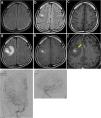

We report a case of gamma knife surgery (GKS)-induced chronic encapsulated expanding hematoma with extensive literature review. A 17-year-old young man underwent GKS after embolization for arteriovenous malformation (AVM) in the right frontal lobe and the AVM completely disappeared. He developed a generalized convulsion 15 years after GKS. MRI showed a small oedematous change at the AVM site. His epileptic seizure was controlled with anticonvulsant. His epilepsy recurred after three years, and MRI revealed an intracerebral hematoma with extensive surrounding edema at the same lesion. He underwent cerebral angiography and a recurrence of AVM was prevented. The hematoma was surgically removed, and intraoperative finding confirmed an old hematoma with a capsule and capillary hyperplasia, without developing cavernous angioma. The final diagnosis was a secondary chronic encapsulated expanding hematoma after GKS. This is the first report to show the early-stage imaging findings of this late effect after GKS.